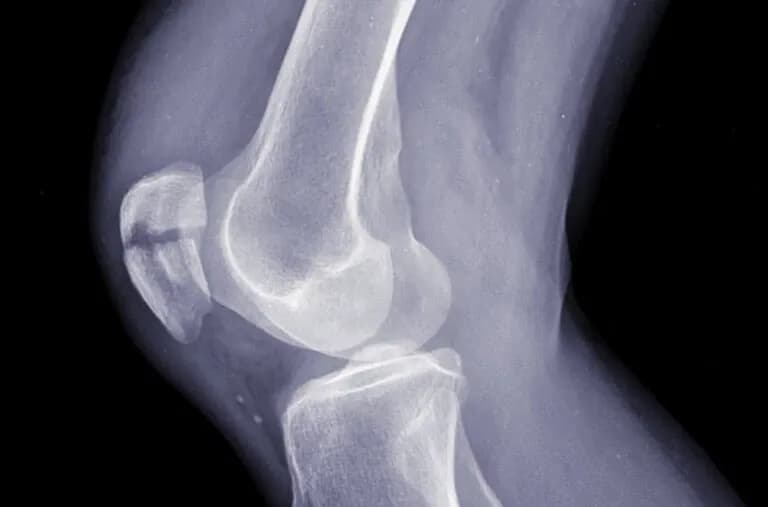

- Diagnostyka obu urazów wymaga badań klinicznych i obrazowych, takich jak rentgen czy MRI.

Zwichnięcie to poważny uraz stawu, który występuje, gdy powierzchnie stawowe kości zostają całkowicie oddzielone. W wyniku tego dochodzi do przesunięcia kości względem siebie, co prowadzi do deformacji kończyny oraz intensywnego bólu. Osoba z zwichnięciem może zauważyć, że staw jest deformowany i ma ograniczoną zdolność ruchu. Objawy te mogą być bardzo nieprzyjemne i znacząco wpływać na codzienne funkcjonowanie.

Rozpoznanie zwichnięcia opiera się na kilku charakterystycznych objawach. Najczęściej występują silny ból w okolicy stawu, obrzęk oraz widoczna deformacja kończyny. Osoba może również odczuwać trudności w poruszaniu stawem, a w niektórych przypadkach może wystąpić zasinienie w wyniku uszkodzenia tkanek miękkich wokół stawu. Ważne jest, aby zwracać uwagę na te objawy, ponieważ ich obecność może wskazywać na poważny uraz.